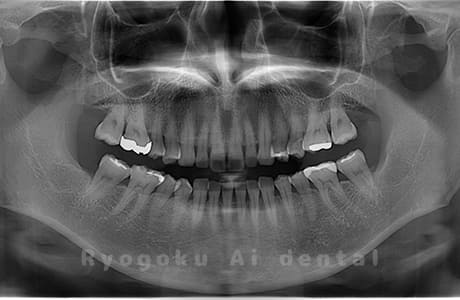

Case04

- 原因

- 上顎の親知らず、下顎の水平埋伏の親知らず

- 治療内容

- 上顎の親知らず、下顎の水平埋伏の親知らずを抜歯したケースです。

<リスク・副作用>

手術後は痛み、腫れ、痺れなどの副作用が生じる場合があります。